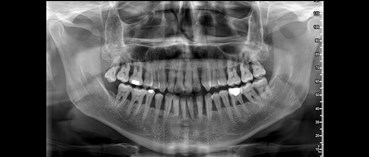

Η πανοραμική ακτινογραφία αποτελεί μια διαδεδομένη ακτινογραφική εξέταση, επειδή απεικονίζει ολόκληρη τη στοματογναθοπροσωπική περιοχή. Η πανοραμική ακτινογραφία είναι η μοναδική ακτινογραφική τεχνική που δίνει τη δυνατότητα στον Οδοντίατρο να δει σε μια εικόνα όλα τα δόντια και τα οστά τόσο της άνω όσο και της κάτω γνάθου, καθώς και τις κροταφογναθικές διαρθρώσεις.

Η συνολική και με ακρίβεια ακτινογραφική εικόνα του στόματος σε συνδυασμό με την προσιτή τιμή, κάνει την πανοραμική ακτινογραφία ένα από τα βασικότερα διαγνωστικά βοηθήματα της οδοντιατρικής.

Ενώ ο τρόπος λήψης της ψηφιακής πανοραμικής ακτινογραφίας είναι αρκετά απλός και πραγματοποιείται με μια πλήρη περιστροφή του πανοραμικού μηχανήματος γύρω από την κεφαλή του ασθενούς, η δημιουργία της εικόνας είναι αρκετά περίπλοκη διαδικασία. Η πανοραμική δοντιών είναι μια απολύτως ασφαλής και ανώδυνη εξέταση, με εξαιρετικά προσιτό κόστος. Βασική προϋπόθεση για την ορθή λήψη της πανοραμικής ακτινογραφίας είναι η σωστή τοποθέτηση του εξεταζόμενου στο πανοραμικό μηχάνημα, ώστε να εξαλειφθούν ανεπιθύμητες επιπροβολές στις περιοχές ενδιαφέροντος.